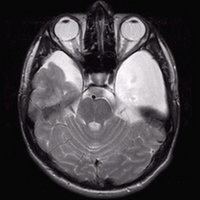

Arachnoidalzyste

Arachnoidalzyste T1 transversal